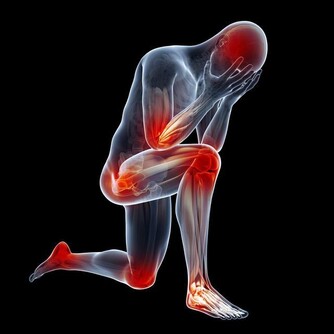

腳是用來走路的,人這一輩子總是會走很遠的路,而且每前進一步腳部就會承受的重量大概為自身體重的3-5倍。但很多人平時很容易忽視腳部,甚至連最起碼的泡腳、皮膚護理都做不到。

如果你發現雙腳出現以下6個症狀,千萬不要忽視,因為這往往是身體在發出“求救”信號:

*****四、腳麻*****

平時腳麻大部分情況下都是因為某一個姿勢導致血液循環不暢引起,這時候改變一下姿勢,緩解一段時間就可以恢復。但是雙下肢以及腳部麻木也是糖尿病臨床的表現之一,這與糖尿病對於末梢神經以及血管的損傷有關。

*****五、腳冰涼*****

如果你在溫度比較適宜的環境下依舊會出現腳部冰涼的症狀,就意味著下肢的血液循環出現了異常,這與久坐久站或者缺乏運動有關,也可能與動脈硬化、下肢靜脈血栓等疾病有關,因為這類疾病會導致局部的血液循環不暢,所以就會有腳部冰涼的症狀。